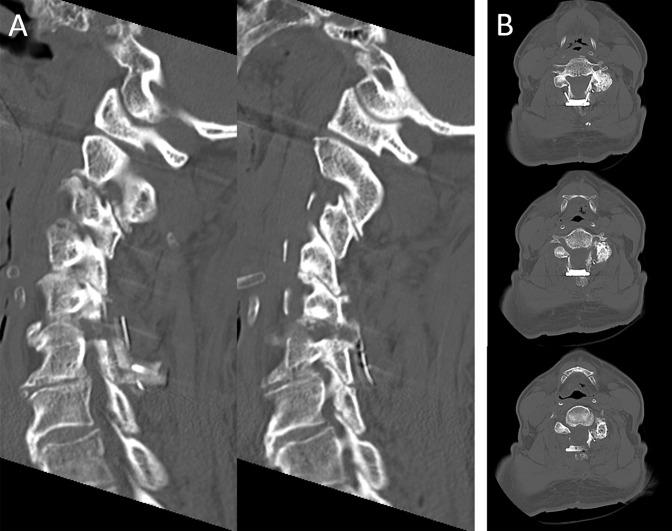

增强现实可视化引导下的显微镜脊柱手术:经椎间隙前路颈椎椎间孔切开术和后路椎间孔切开术。

Augmented Reality Visualization-guided Microscopic Spine Surgery: Transvertebral Anterior Cervical Foraminotomy and Posterior Foraminotomy.

We describe intraoperative augmented reality (AR) imaging to obtain a microscopic view in spine keyhole surgery.

Minimally invasive keyhole surgery has been developed even for spine surgery, including transvertebral anterior cervical foraminotomy and posterior cervical laminoforaminotomy. These methods are complex and require a skillful technique. Therefore, inexperienced surgeons hesitate to perform keyhole surgeries. The technology used in surgery is rapidly advancing, including intraoperative imaging devices that have enabled AR imaging and facilitated complicated surgeries in many fields. However, data are not currently available on the use of AR imaging in spine surgery. The purpose of this article was to introduce the utility of AR for spine surgery.

We performed O-arm intraoperative imaging to create an augmented imaging model in navigation systems. Navigation data were linked to a microscope to merge the live view and AR. Augmented reality imaging shows the model plan in the real-world surgical field. We used this novel method in patients who underwent both keyhole surgeries.

We successfully performed both surgeries using the AR visualization guide.

The AR navigation system facilitates complicated keyhole surgeries in patients who undergo spine surgery.

我们描述了术中增强现实(AR)成像技术,以在脊柱锁孔手术中获得微观视野。

即使是脊柱手术,包括经椎体前路颈椎椎间孔切开术和后路颈椎椎板间孔切开术,也已发展出微创锁孔手术。这些方法操作复杂,需要熟练的技术。因此,经验不足的外科医生对进行锁孔手术犹豫不决。手术中使用的技术正在迅速发展,包括术中成像设备,这些设备已实现AR成像,并在许多领域促进了复杂手术的开展。然而,目前尚无关于AR成像在脊柱手术中应用的数据。本文的目的是介绍AR在脊柱手术中的实用性。

我们进行了O型臂术中成像,以在导航系统中创建增强成像模型。将导航数据与显微镜相连,以融合实时视野和AR。增强现实成像在真实的手术视野中显示模型规划。我们在接受两种锁孔手术的患者中使用了这种新方法。

我们使用AR可视化引导成功完成了两种手术。

AR导航系统有助于为接受脊柱手术的患者进行复杂的锁孔手术。